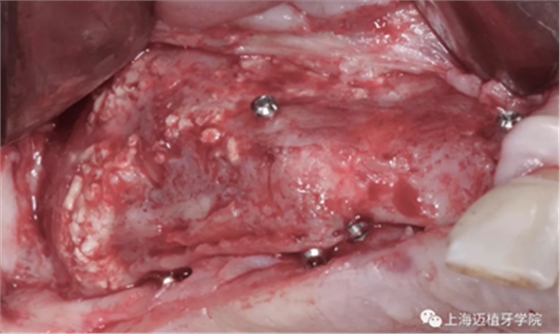

利用BBA植骨法,骨片固定頰舌側距離

GBR骨生物材料植骨失敗后,利用BBA植骨法及軟組織處理病例

中間填充自體骨屑

用骨釘固定骨板